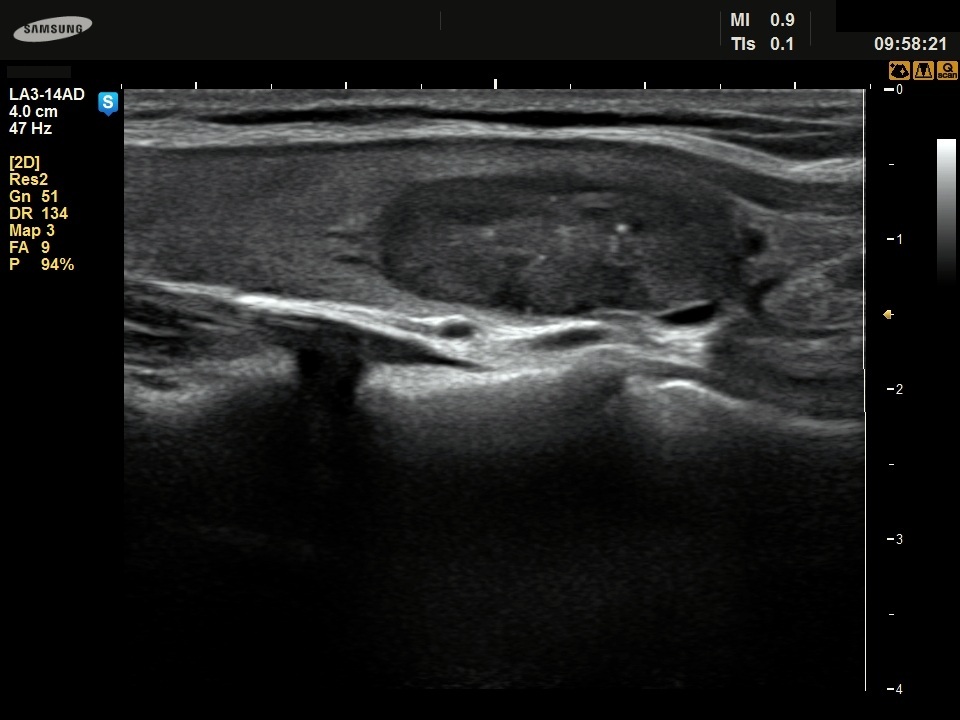

Ethanol sclerotherapy: thyroid cysts - Case 11

Four years after the sclerotherapy (ultrasonographic picture 2)

Left lobe, longitudinal scan. There are various hyperechogenic figures within the lesion.